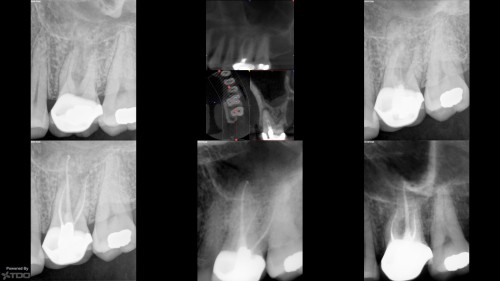

In today regarding this tooth I treated in 2005. Stepped access, two step crown repair […]

Three year followup on NSRCT with amalgam crown repair